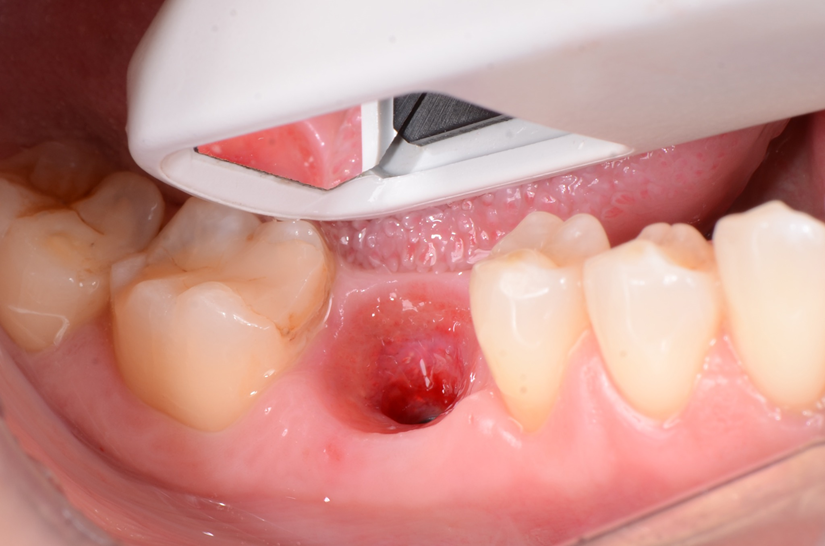

O paciente apresentou fratura vertical mésio-distal no elemento 46. Foi planejada a exodontia minimamente traumática e instalação imediata do implante Maestro Superiore (Implacil Osstem) utilizando uma guia prototipada. Após a exodontia, o implante foi instalado seguindo o protocolo de cirurgia guiada. O GAP vestibular foi preenchido com o Extra Graft. Um cicatrizador personalizado impresso com haletas facilitadoras foi capturado com resina flow e instalado. Após 30 dias, foi realizado escaneamento indireto para obtenção do perfil de emergência, utilizando protocolo digital com sobreposição do cicatrizador escaneado para confecção da coroa definitiva em zircônia policristalina estabilizada por ítria.

O uso de cicatrizadores personalizados, especialmente confeccionados por impressão 3D, tem ganhado destaque por permitir a conformação tecidual progressiva, facilitando a reprodução do perfil de emergência no fluxo digital6,7. A captura do cicatrizador com haletas de retenção com resina flow e seu posterior escaneamento são etapas críticas para assegurar a fidelidade da transferência do perfil de emergência e garantir um planejamento restaurador mais previsível8.

Neste caso, a sobreposição digital entre o cicatrizador escaneado e o desenho da coroa possibilitou comparar perfis de emergência com excelente adaptação clínica, contribuindo para um resultado estético e funcional adequado.